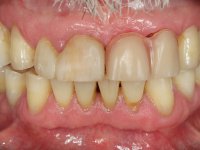

Paciente do sexo masculino, com 64 anos de idade, não fumador, recorreu á minha consulta após traumatismo do sector anterior. Os dentes 2.1 e 2.2 apresentavam extensas fraturas infra ósseas. Os dentes 1.2 e 1.1 apresentavam-se ferulizados com uma resina composta na zona inter-proximal. O dente 1.1 apresentava um tratamento endodôntico sofrível e um poste intra-radicular. O dente 1.2 estava vital e tinha uma extensa restauração da resina composta. Estando ferulizados, não foi possível avaliar o grau de mobilidade dentária de cada um dos dentes, mas o conjunto não tinha mobilidade. Após exame clínico e Imagiológico conclui-se que as raízes dos dentes 2.1 e 2.2 tinham extração indicada. O paciente estava reabilitado provisoriamente com uma prótese removível esquelética com 3 dentes. Apresentava algum comprometimento periodontal e os dentes mostravam as superfícies oclusais e incisais desgastadas. Higiene oral razoável.

Foi proposta a extração das raízes dos dentes 2.1 e 2.2. e colocação de 1 implante no local do dente 2.1 que suportaria uma ponte aparafusada com 2 elementos. O dente 2.1 sobre o implante e o 2.2 em extensão. Se em termos periodontais a zona do 1.2 e 1.1 continua-se a maturar sem problemas e se garantir-se um bom suporte sem mobilidade, seria proposto refazer o tratamento endodôntico do 1.1 e fazer o tratamento endodôntico no 1.2. Posteriormente e após colocação de postes intra-radiculares os dentes seriam reabilitados com uma ponte com 2 elementos. Após a colocação da ponte de2 elementos sobre o implante colocado no local do 2.1, o paciente sofre um novo traumatismo que compromete a viabilidade dos dentes 1.2 e 1.1. Nessa altura é proposta a colocação de um novo implante no local do dente 1.1 e confeção de uma ponte de 4 elementos com os dentes 1.1 e 2.1 sobre os implantes e os dentes 1.2 e 2.2 como pônticos em extensão.